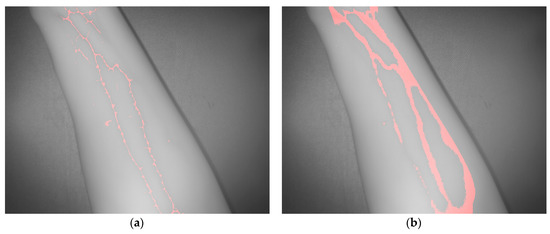

2.2. Algorithm for Automatic Detection and Localization of Peripheral Subcutaneous Veins